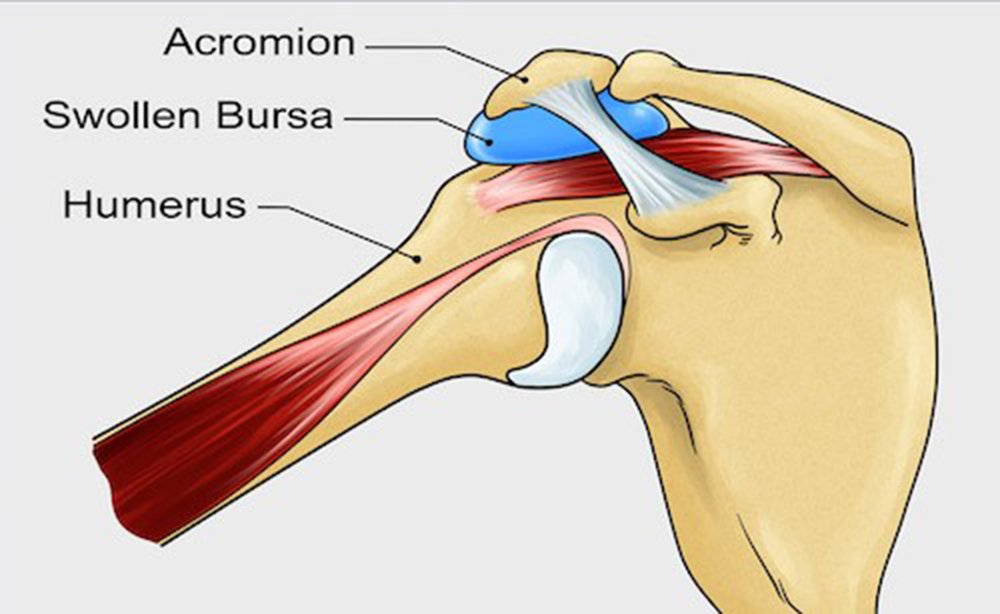

- Location : The subacromial bursa is situated between the acromion, a bony projection of the scapula, and the rotator cuff tendons. This space forms the roof of the shoulder joint.

- Composition : The bursa is a thin, lubricated sac filled with synovial fluid. Synovial fluid is a clear, viscous fluid that helps reduce friction and allows smooth movement between adjacent structures.

- Function : The primary function of the subacromial bursa is to facilitate movement and reduce friction between the acromion, rotator cuff tendons, and other soft tissues in the shoulder. It acts as a protective cushion, preventing irritation and inflammation during shoulder movement.

- Relations : The bursa is closely related to the rotator cuff tendons, including the supraspinatus tendon. It lies beneath the acromion and the acromioclavicular joint, forming a protective layer between these structures.

- Bursitis : Inflammation of the subacromial bursa, known as subacromial bursitis, can occur due to various reasons, such as overuse, trauma, or age-related changes. Bursitis can lead to pain, swelling, and limited range of motion in the shoulder.

- Impingement Syndrome : The subacromial space can narrow, causing impingement of the rotator cuff tendons and the subacromial bursa between the acromion and the head of the humerus. This can result in pain and inflammation, especially during overhead activities.

- Narrowing of the Subacromial Space : Impingement occurs when the space between the acromion and the head of the humerus narrows, leading to compression of the subacromial bursa and the rotator cuff tendons during certain shoulder movements. This can result from anatomical variations, bone spurs, or muscle imbalances.